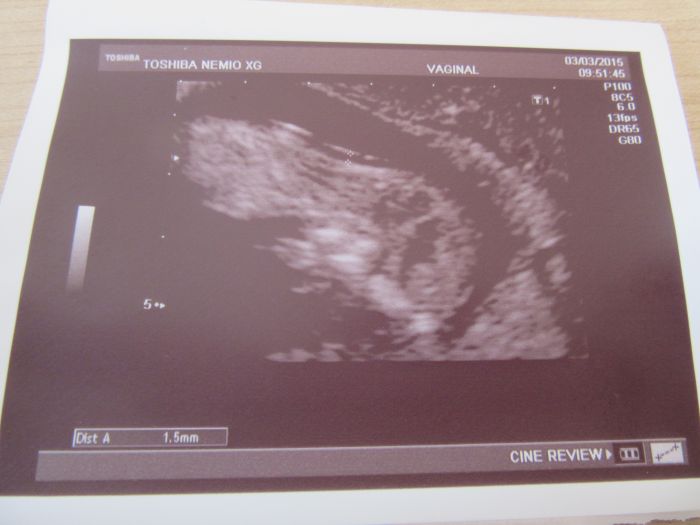

Ahoj holky, tak to dneska klaplo, jsem šťastná. Screening dopadl dobře, vše je v naprostém pořádku a za 14 dní se dozvím jak dopadla krev, pokud se jim něco nebude líbit tak se ozvou. Jinak mně vše ukázal i jak mám plný nacpaný žaludeček, to jsem teda koukala, nebude to zatím žádný divoch,jen trošičku se tam hýbal, ale moc tomu nedal. Jsem dnes 12+1 a měříme 5,53cm. Přikládám fotečky. Máme už hotové oznámení tak také přikládám fotečky hotového výrobku.

Kačko, gratulace, krása! Byl s tebou budoucí tatínek? A koukám, že na tom obrázku máš napsáno "vaginal" - to ti to dělali spodem? To muselo být něco, protože mě do toho břicha při vyšetření dost šťouchali a spodem bych si to nedovedla představit...